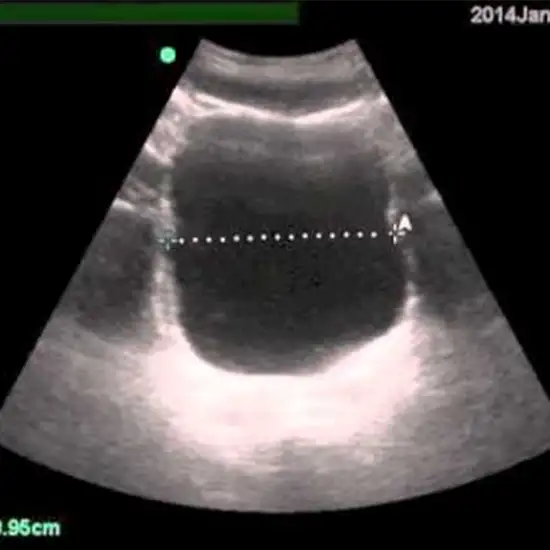

Post Void Residual (PVR) and Bladder Ultrasound is a non-invasive procedure that uses sound waves for the detection of abnormalities in the bladder. This procedure is for patients with urine retention issues (inability to empty the bladder). Post-void residual measurement is a method for determining how much pee remains in the bladder after urinating (or voiding). Post-void residual (PVR) urine volume is the amount of urine remaining in the bladder following urination.

A U/S Post Void Residual is performed at a healthcare facility, patient will be kept flat on the table for examination. A device called a probe or transducer is moved over the abdominal area containing the bladder for the examination and the gel is used for smooth and good test-quality images. The procedure gives a detailed view of the bladder condition. Ultrasound produces the pictures and gives an examination of the bladder in detail.

Ultrasound PVR is a painless, rapid, non-invasive and safe technique that is used to examine the urinary bladder for urinary retention.

Ultrasound PVR is a safe procedure with no side effects as it utilizes sound waves and a computer to produce images of the urinary bladder which help in the estimation of residual urine that remains in your bladder post-voiding.